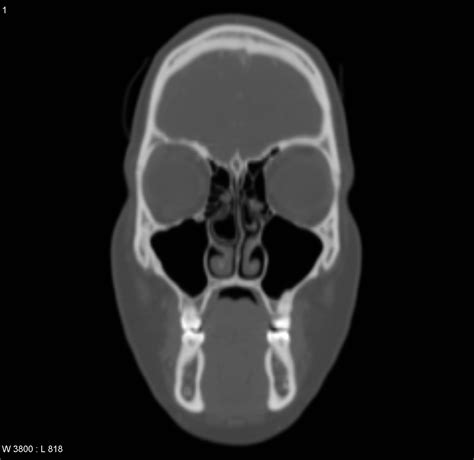

Diagnosing a Concha Bullosa typically requires more than a simple visual inspection during a physical exam. While an ENT might suspect the condition using an endoscope—a thin, flexible tube with a camera—a definitive diagnosis almost always relies on imaging. A Computed Tomography (CT) scan of the paranasal sinuses is the gold standard. It provides a detailed cross-sectional view of the nasal architecture, allowing the physician to measure the exact size of the air pocket and determine if it is contributing to sinus obstruction.

CT Scan Detailed imaging to confirm pneumatization and identify potential obstruction sites.

• concha bullosa ct scan

• concha bullosa ct sinus